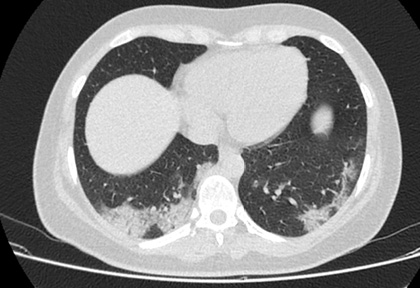

Routine clinical laboratory assays were performed in the hospital’s clinical laboratories. Clinical and laboratory information was extracted from the patients’ medical records. C reactive protein (CRP) in plasma was measured by immunoturbidimetry (Beckman Coulter, Krefeld, Germany). Interleukin-6 (IL-6) levels in plasma were measured by electrochemiluminescence (Siemens Medical Solutions Diagnostics, Siemens Healthcare, Erlangen, Germany). CT scans were read by experienced radiologists who scored results by severity using the criteria shown in Figure 1.

Figure 1. Clinical assessment of pneumonia severity based on computed tomography (CT) scores.

Scoring method: Mild (CT-1)—no more than three ground-glass opacities of <3 cm maximum diameter. Moderate (CT-2)—more than three ground-glass opacities; less than 50% involvement by visual assessment. Medium-heavy (CT-3)—ground-glass opacities and pulmonary consolidation; 50-70% involvement by visual assessment. Severe (CT-4)—diffuse ground-glass opacities with or without consolidation; more than 75% involvement by visual assessment.